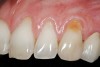

A 27-year-old non-smoking man presented for esthetic enhancement of the left central incisor, which had a pre-existing full-coverage restoration that required replacement (Figure 16). The patient had begun orthodontic treatment in the mandibular arch to correct a minor occlusal imbalance and required coronal repositioning and soft tissue grafting to correct gingival recession at the facial of the right canine, in addition to correction of the free gingival margin at the facial of the left central incisor, which was asymmetrical to the free gingival margin of tooth No. 8. Additionally, the facial gingival tissues were of a thin biotype, which at the facial surface of the left central incisor allowed for the darkened root surface to be visible through the tissue (Figure 16).

The treatment plan was to accomplish an increased zone of keratinized tissue at tooth No. 6, and increase the thickness of the facial tissue at tooth No. 9, in addition to coronally repositioning the free gingival margin. Complicating this treatment plan was the fact that at the facial surface of tooth No. 9, a biologic width invasion was present due to the prepared margin for the pre-existing restoration being placed too close to the facial alveolar crest of bone (the patient had presented to the periodontist with a provisional restoration in place). Any correction to the area would require movement of the facial margin of the tooth in a coronal fashion to re-establish the appropriate distance from the facial height of bone to the margin of the restoration. Additionally, options were given to the patient for harvesting the soft tissue, using connective tissue from the palate, or the use of an acellular dermal matrix graft, which would nullify harvesting tissue from the palate region.

Figure 16  Case Two Preoperative clinical view, maxillary left central incisor.

Figure 16